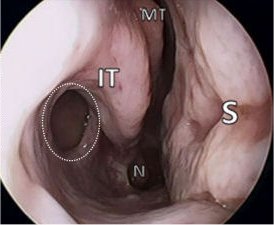

Si vos symptômes ne disparaissent pas avec le traitement prescrit par votre médecin de famille, vous pourrez être adressé(e) à un otorhinolaryngologiste (ORL). Ce spécialiste des oreilles, du nez et de la gorge utilisera un endoscope nasal pour explorer l'intérieur de votre nez. Un endoscope est un instrument très fin, muni à son extrémité d'un dispositif lumineux ;

Pendant l'opération, l'ORL introduit un tube fin, appelé endoscope, dans votre nez. Ce tube est

muni à son extrémité d'une minuscule caméra et d'un dispositif lumineux, afin que le chirurgien puisse visualiser votre sinus maxillaire, l'ouverture du sinus maxillaire et sa zone de drainage (le complexe ostéoméatal). Puis de petits instruments chirurgicaux sont amenés jusqu'au site du problème.

Cette opération s'effectue généralement sous anesthésie générale. Elle dure 1 à 3 heures, selon

votre état. Pendant l'opération, votre ORL introduit un tube fin appelé endoscope dans votre nez. Ce tube est muni à son extrémité d'une minuscule caméra et d'un dispositif lumineux, ce qui permet au chirurgien de visualiser votre septum et vos cornets. De petits instruments chirurgicaux sont amenés jusqu'au site du problème.